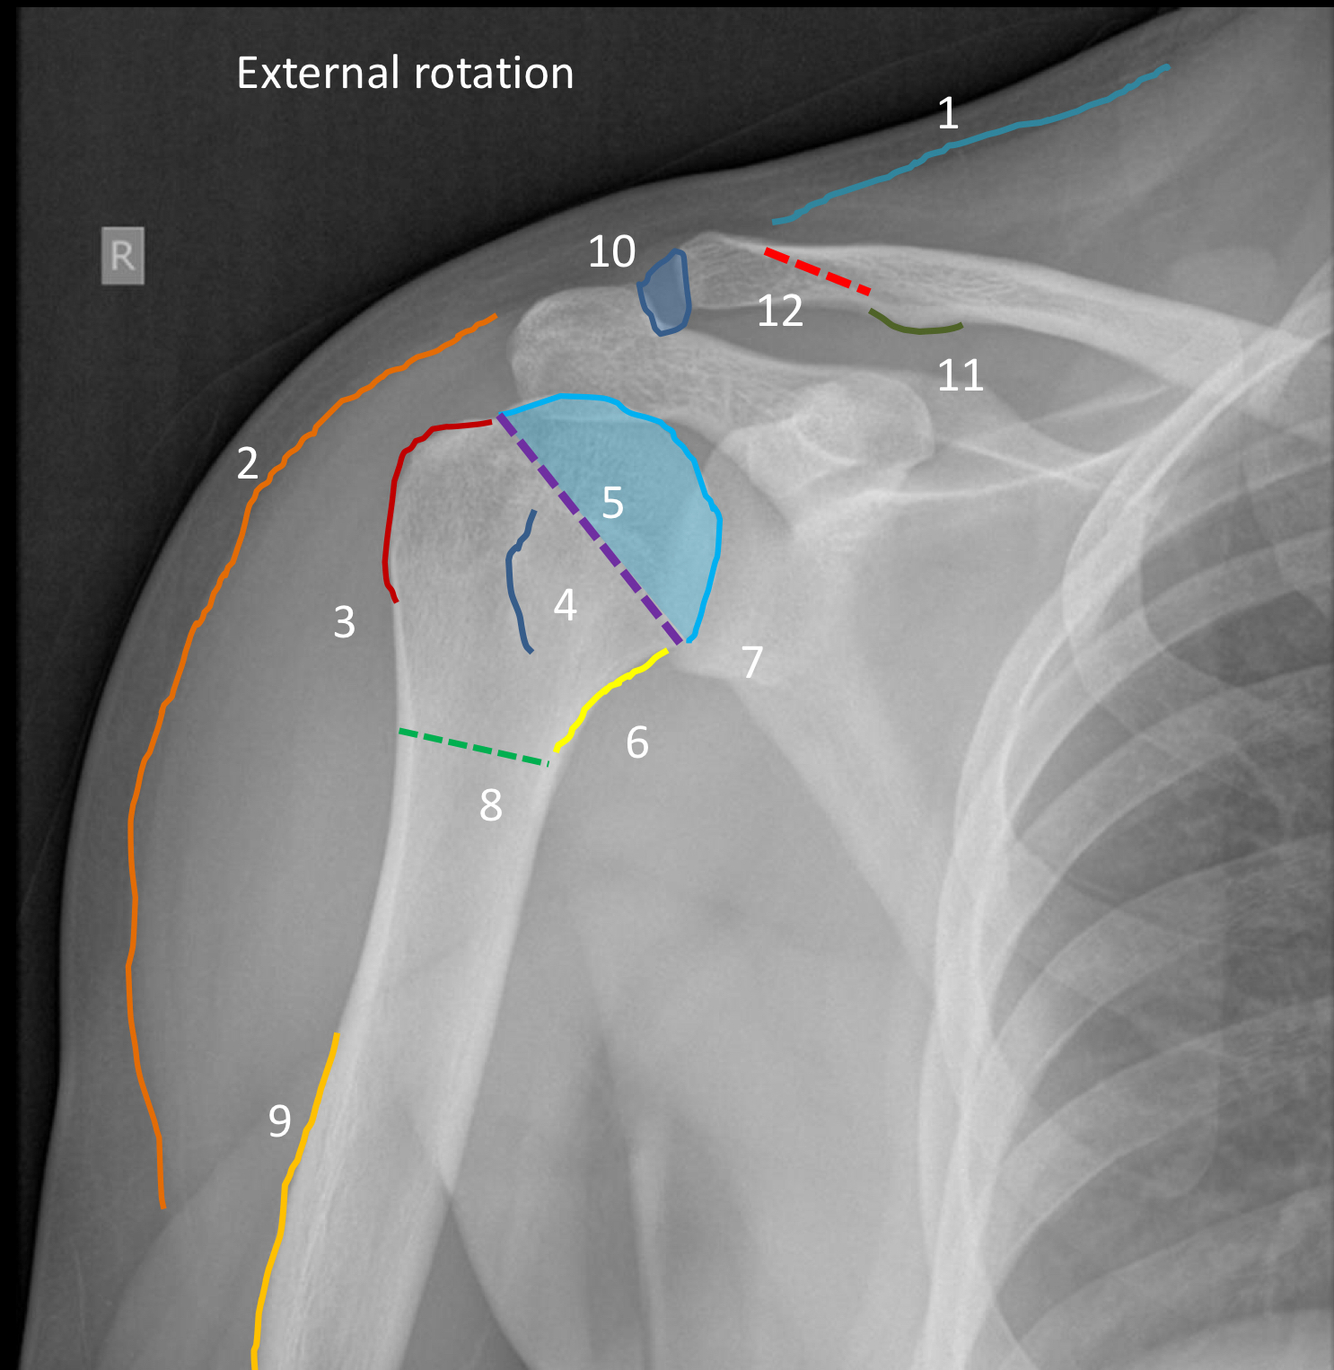

What view is this?

AP shoulder with external rotation

1?

superior margin of trapezius muscle

2?

lateral margin of deltoid muscle

3?

greater tuberosity of the humerus

4?

lesser tuberosity of the humerus

5?

humeral head

6?

medial margin of humeral metaphysis

7 (dotted purple line)?

anatomical neck of humerus

8 (green dotted line)?

surgical neck humerus

9?

deltoid tuberosity

10?

acromioclavicular joint space

11 (dark green line)?

conoid tubercle

12?

trapezoid line or ridge of clavicle